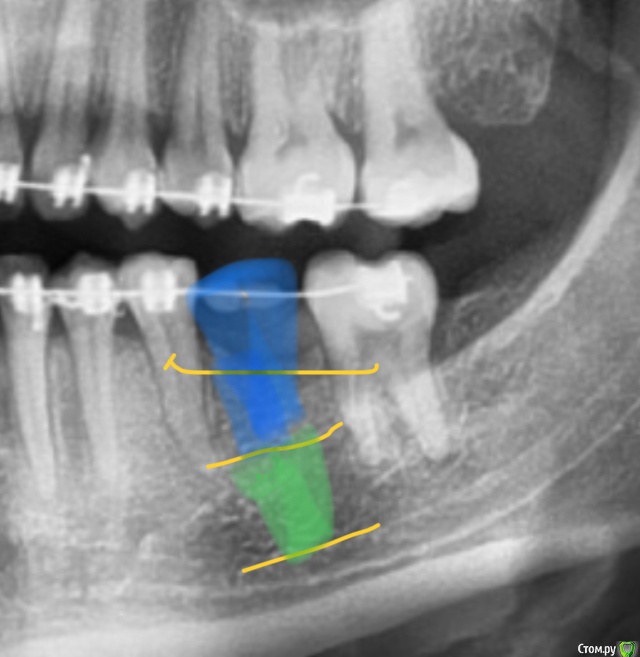

колесников Опубликовано 15 ноября, 2019 Поделиться Опубликовано 15 ноября, 2019 Вот так это будет выглядеть в третьем варианте. Так себе вариант Ссылка на комментарий

krokomot Опубликовано 15 ноября, 2019 Поделиться Опубликовано 15 ноября, 2019 Вот так это будет выглядеть в третьем варианте. Так себе вариантколлега на мой взгляд вы немного утрируете, по вершине гребня примерно 3.5 мм, на 1 мм от гребня 4 мм... Ссылка на комментарий

колесников Опубликовано 16 ноября, 2019 Поделиться Опубликовано 16 ноября, 2019 Посмотрите внимательней. 4 мм начинается от уровня тела челюсти. Измеряем конечно от внутренней стенки компактной пластинки Ссылка на комментарий